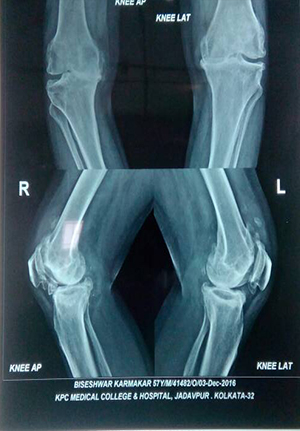

Reduction and internal fixation for proximal tibial fracture

before operation

After operation